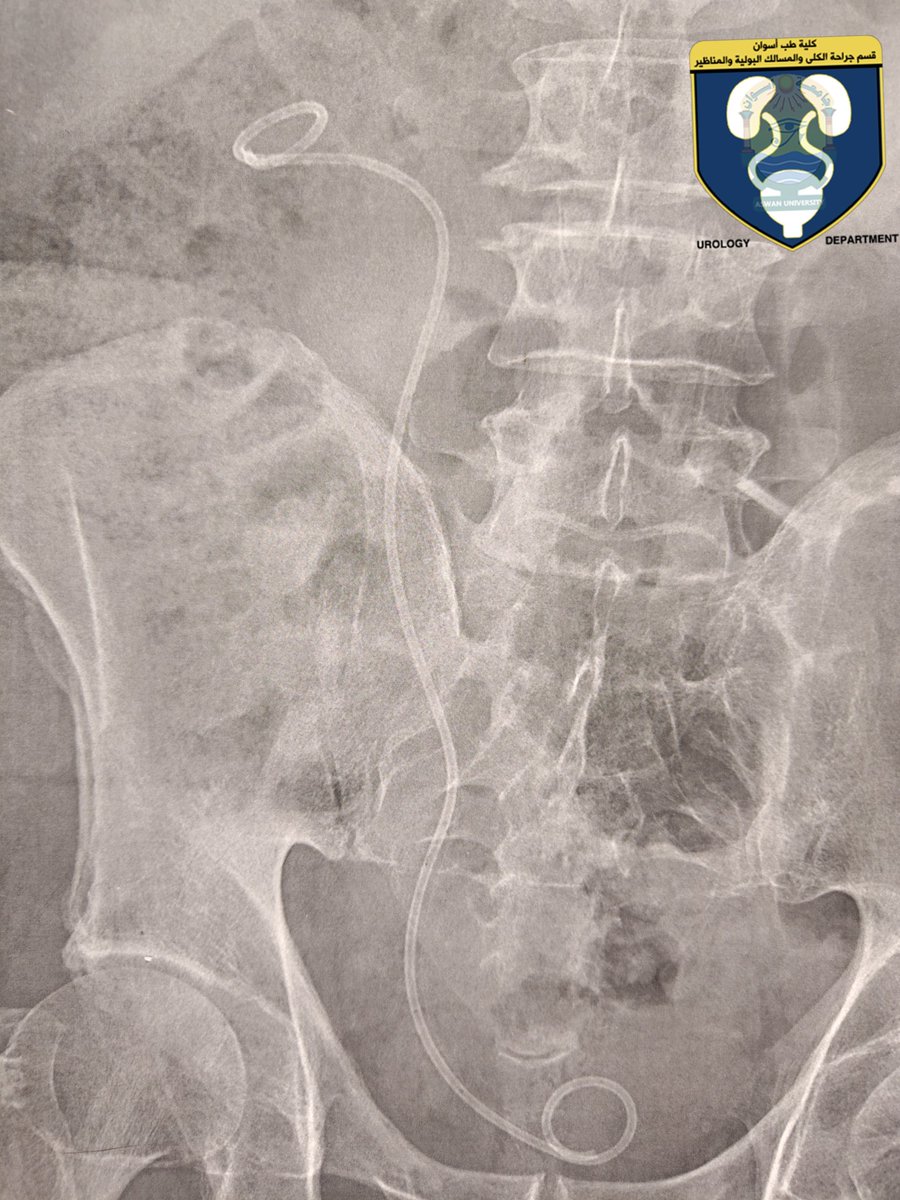

My rare case report was published

(Intracardiac migration of ureteral double-J stent)

1st case reported in Egypt

10th case reported all over the world